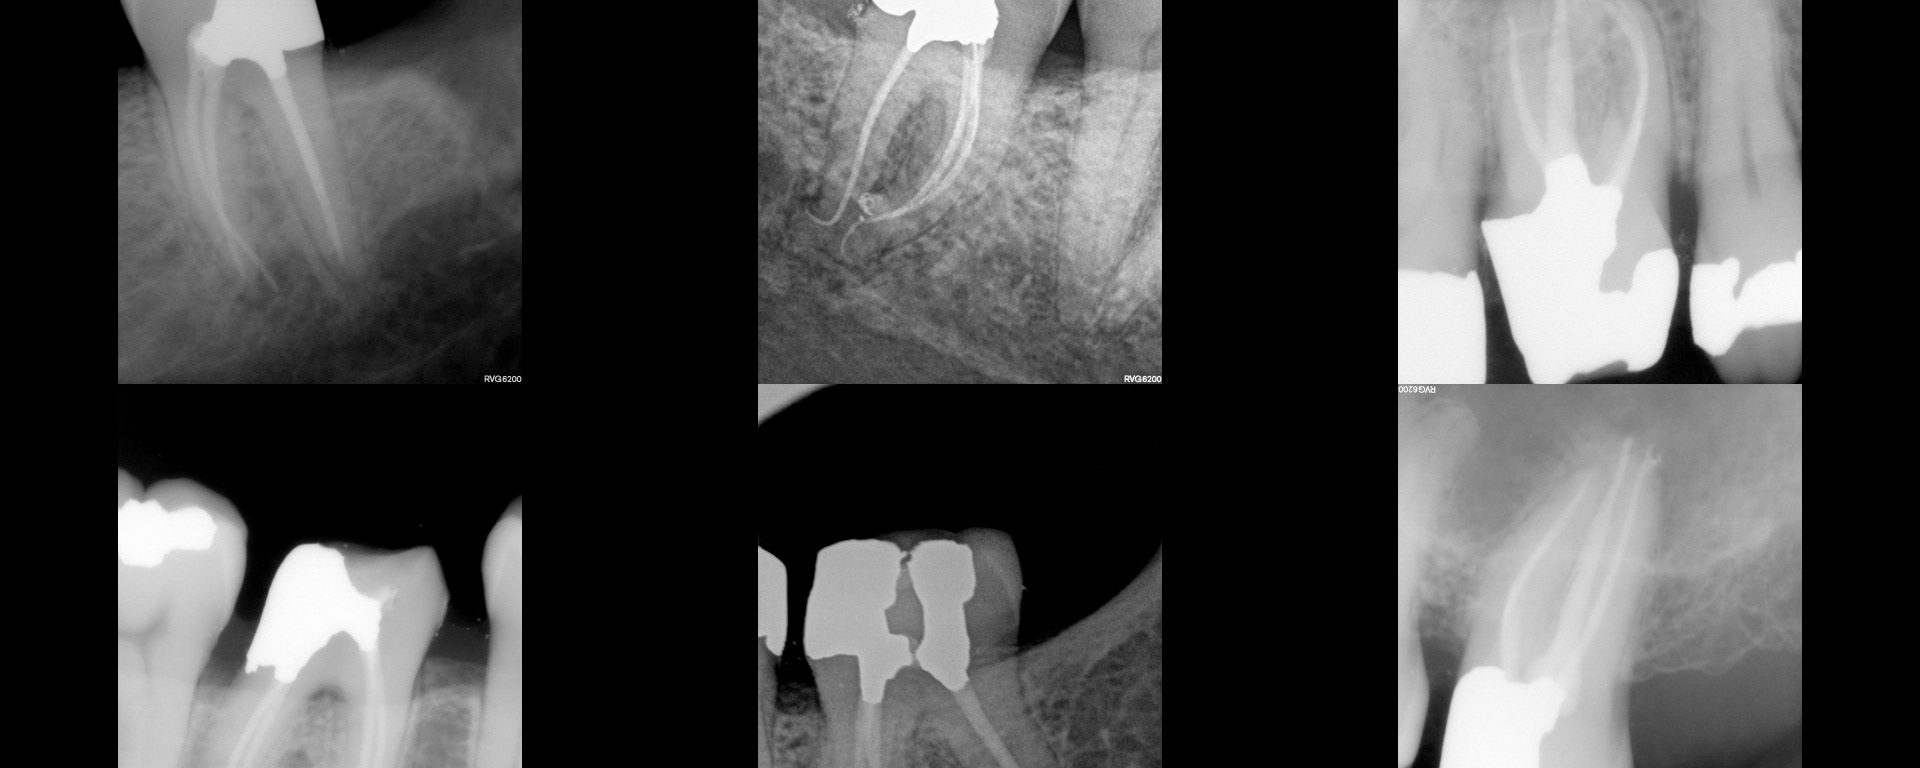

If you ever get an opportunity to work with Tucker gold people, take it….because they do dentistry that lasts a lifetime. This is some work from Phil Timmins, a Tucker gold guy.

This was a pt I saw Dec 2015 with extensive coronal ICR. It really did not seem to go much below the CEJ, but the anatomical crown was pretty much hollow. Patient insisted she did not want to extract the tooth, so we did RCT. Followed Heithersay protocol with TCA. She is completely asymptomatic and […]

White , 70 yo, male presented completely asymptomatic but with a buccal ST. Tooth had a post and crown and patient did not want to have it removed. CBCT showed missed palatal canal. Access was done above the P cusp with the intention of locating and treating the missed canal only. Last PA is a […]

Not very happy with my distal margin….don’t think I have the right kind of burs for this. This is hard….at least for me…..The decay was sub-osseous on both sides. The temp was a 3/4 onlay where the B cusps were preserved. gbc